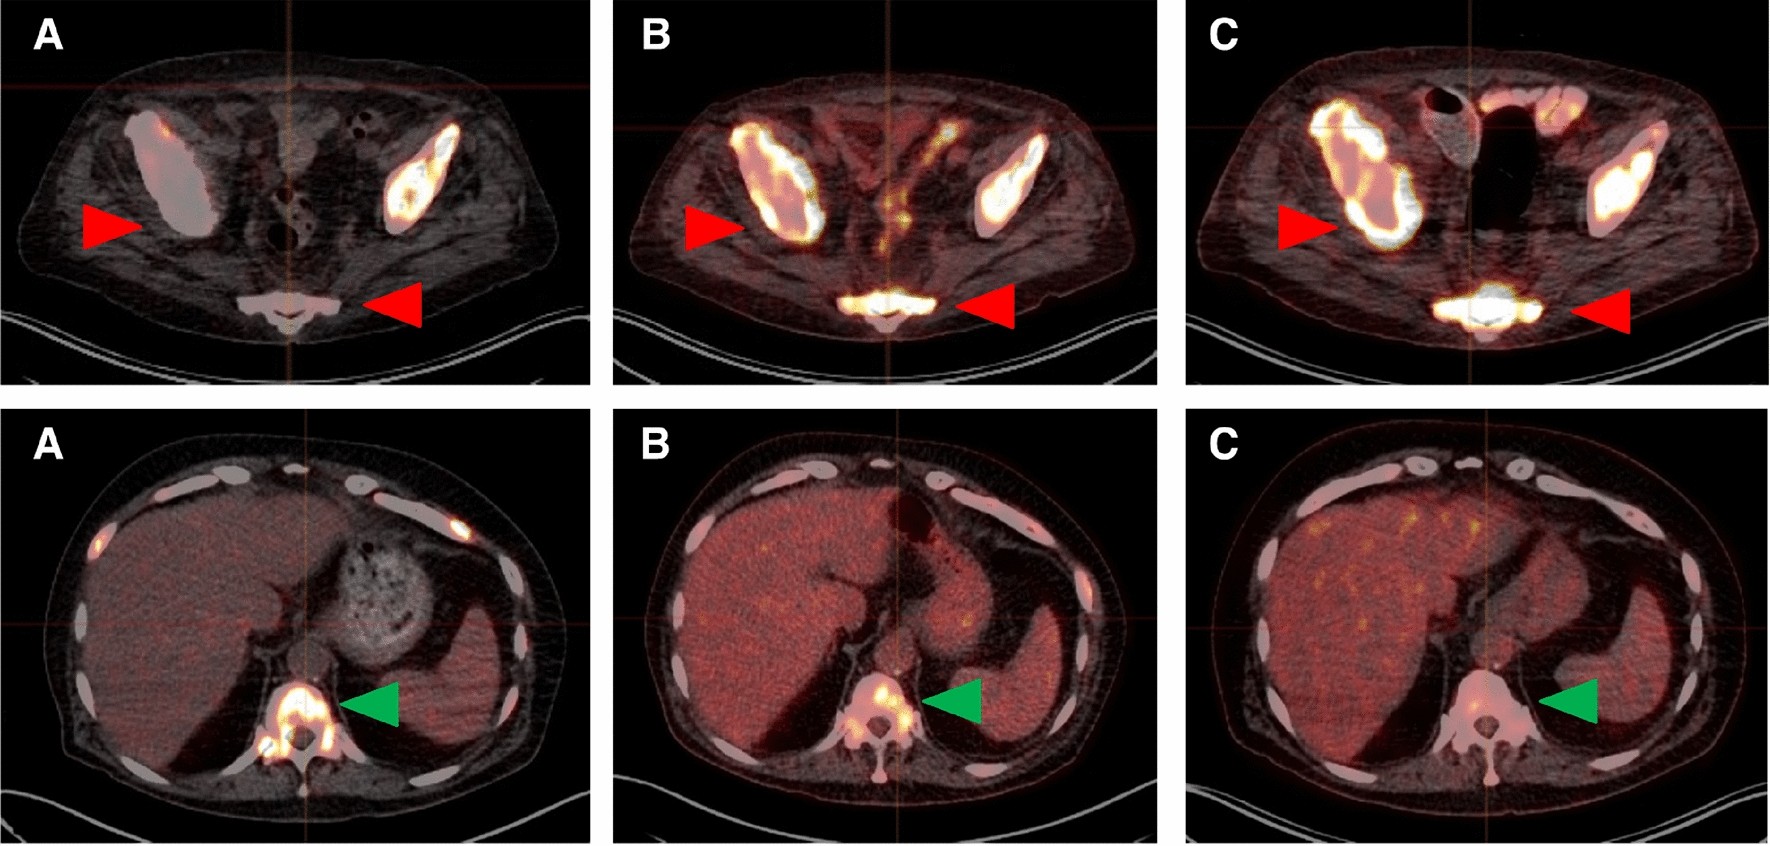

Representative transverse slice images showing lesion-based progression (first row) and partial response (second row) to 2 cycles of [177Lu]Lu-PSMA-617 RLT: (A) baseline [68Ga]Ga-PSMA-11 PET/CT, (B) baseline [18F]FDG PET/CT, and (C) follow-up [18F]FDG PET/CT. First row, red arrows: progressing bone metastases. These lesions had faint [68Ga]Ga-PSMA-11 uptake (SUVmax: 3.47 and 4.00, respectively) and intense [18F]FDG uptake (SUVmax: 11.17 and 8.67, respectively) in the baseline scans (FPQ: 3.22 and 2.17, respectively), and increased [18F]FDG uptake (SUVmax 16.87 and 12.37, respectively; 51% higher and 43% higher, respectively, than at baseline) in the follow-up scan. Second row, green arrows: bone metastasis showing partial response. The lesion, which had intense [68Ga]Ga-PSMA-11 uptake (SUVmax: 22.74) and moderate [18F]FDG uptake (SUVmax: 6.60) in the respective baseline scans (FPQ: 0.29), had decreased [18F]FDG uptake (SUVmax 4.52, 32% lower than at baseline) in the follow-up scan.